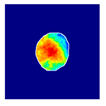

| True label: Crescentic |  |  |  |  |  |

| single-multiclass: Crescentic p = 0.999, IoU = 0.154 | |||||

| multiple-binary: Crescentic p = 1.000, IoU = 0.128 | |||||

| Spatially guided: Crescentic p = 0.979, IoU = 0.740 | |||||